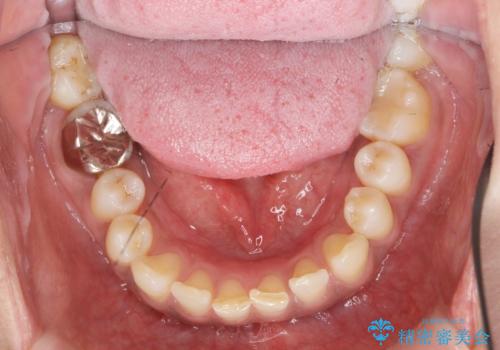

- 笑った時に目立つ銀歯を改善したいとのことで来院されました。

保険適応の銀歯を除去し虫歯を取ったのち、ジルコニアクラウンで置き換えていきます。